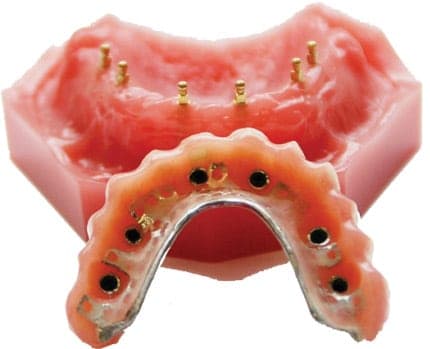

Our office is equipped with the most advanced dental technology available today including CBCT Cone-beam x-rays, intra-oral cameras, mini dental implants (using Drive Lock Technology), and the most modern dental equipment in order to provide our patients with the highest-quality, minimally invasive care with faster, more accurate results.

We also have the support of our own full-service dental lab to fabricate restorations. This drastically reduces the time it takes to create your new smile and minimizes your wait time between appointments. By utilizing our own state-of-the-art dental lab, we can also ensure all restorations are made in the USA with the highest quality materials and expert craftsmanship.

FADI, FICD, FICOI, DIAMDI. Member ADA, Member AGD, Fellow ICOI, Fellow ICD, Fellow ADI, Member AACD. Dr. Todd Shatkin is the co-founder of Scottsdale Dental and Facial Aesthetics in Scottsdale, Arizona. Dr. Shatkin has been in private practice in dentistry since completing dental school at the University of Pacific. Dr. Shatkin specializes in all types of cosmetic and implant dentistry, including the newest “mini dental implants”, which can be immediately “loaded” with dentures or prosthesis, to offer an immediate solution to loose fitting dentures or one or more missing teeth.